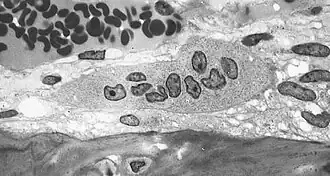

![]() Imagen tomada con un microscopio óptico en la que se observan osteoclastos positivos a la fosfatasa ácida tartrato resistente. | ||

El osteoclasto es una célula multinucleada, móvil y gigante que degrada, reabsorbe y remodela huesos. Al igual que el osteoblasto, está implicado en la remodelación del hueso natural. Deriva de células hematológicas. Los osteoclastos, células responsables de la reabsorción de la matriz ósea, son células acidófilas y polinucleadas de gran tamaño. Ocupan una cavidad llamada laguna de resorción o laguna de Howship y se localizan en las superficies óseas firmemente asociadas a la matriz ósea, por medio de integrinas (α5β3). Los osteoclastos se forman por la fusión de varias células mononucleares derivadas de una célula madre sanguínea de la médula ósea, mostrando muchas propiedades de los macrófagos, formando parte del sistema monocítico macrofágico.

Los osteoclastos se caracterizan por poseer una porción de su membrana "arrugada", en forma de cepillo, rodeada de un citoplasma libre de orgánulos llamada "zona clara", con la que se adhiere a la superficie del hueso mediante integrinas, unos receptores especializados del hueso. El proceso de resorción se inicia cuando el aparato de MRD de las células excreta lisosomas con enzimas capaces de producir un microambiente ácido por debajo de la membrana arrugada como consecuencia del transporte de protones mediante la bomba de protones ATP-dependiente, el intercambio Na+/H+ y la anhidrasa carbónica. Las enzimas lisosomales de los osteoclastos implicadas en este proceso son cistein-proteasas como la catepsina y sobre todo, la fosfatasa ácida tartrato-resistente (esta última se utiliza como marcador del fenotipo osteoclástico). Las enzimas lisosomales solo son liberadas en la zona clara en las proximidades del borde arrugado produciéndose en esta área las reacciones de degradación de la matriz que deben producirse antes de que el medio ácido disuelva las sales minerales del hueso.